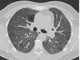

Chronic disseminated air-space opacity

May Be Caused by

Alveolar microlithiasis

Alveolar proteinosis

Aspergillosis

Atypical mycobacterial infection

Bronchiolo-alveolar carcinoma

Choriocarcinoma

Chronic eosinophilic pneumonia

Cryptogenic organizing pneumonia

Desquamative interstitial pneumonitis

Fungal disease

Hemorrhagic lung metastasis

Intralobar pulmonary sequestration

Lipoid pneumonia

Lymphocytic interstitial pneumonitis

Lymphoma

Mineral oil aspiration

Nonspecific interstitial pneumonitis

Obstructive pneumonia

Recurrent pneumonia

Sarcoidosis

Silicoproteinosis

Tuberculosis